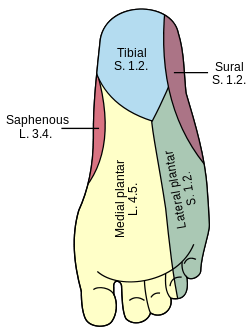

What is the pathway of the tibial nerve?

runs through popliteal fossa

runs with tom dick AN harry though medial malleoulus

bifurcates into medial and lateral plantar nerves

Into which nerves does tibial nerve bifurcate?

medial and lateral plantar nerve

continues onto the dorsum of the foot for sensory innervation in the flip flop area

continues onto the dorsum of the foot

origin course and distribution of saphenous nerve

spinal cord level

O femoral nerve

C descends with femoral vessels through femoral triangle and adductor canal then descends with great saphenous vein

D supplies skin on medial side of leg and foot

L3-L4

origin course and distribution of sural nerve

O formed by the union of the cutaneous banches from the tibial and common fibular nerves

C descends between heads of gastroc; becomes superficial at middle of leg; descends with small saphenous vein; passes inferior to lateral malleoulus to lateral side of foot